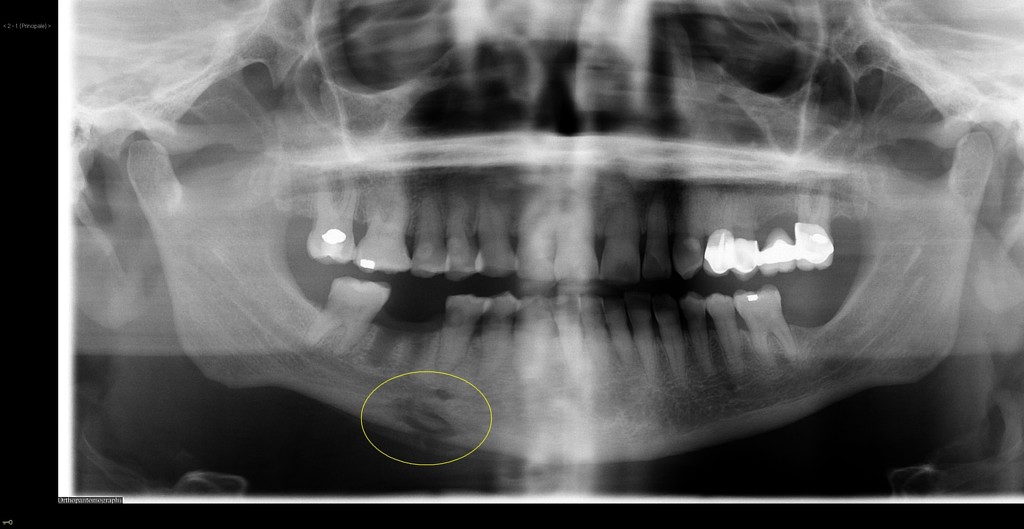

Panoramic dental Xray showing right mandibular osteomyelitis (“lumpy... Download Scientific Acute Osteomyelitis Of Mandible Symptoms of acute osteomyelitis include pain, fever, and edema of the affected site,. Segmental mandibular resection is an effective method for eradicating mandibular osteomyelitis. Nine patients who reported symptoms of no longer than 1 month were classified as having acute suppurative osteomyelitis. Osteomyelitis is an inflammatory condition of bone secondary to infection; Most lesions occurred in the mandible (maxilla :. Acute Osteomyelitis Of Mandible.